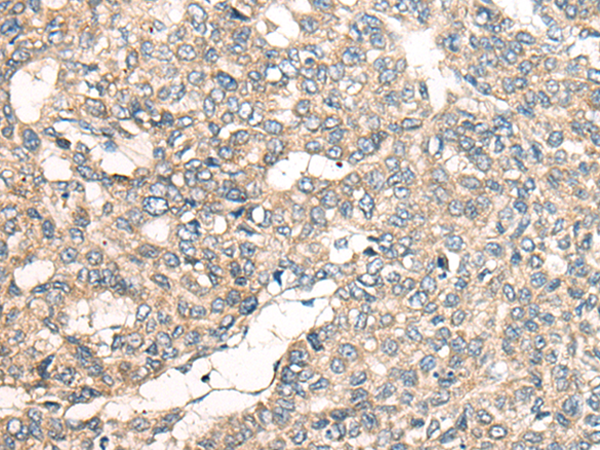

分类: 科研抗体货号: P12875别名: DR11; HH14; BRWD2; WDR15应用: WB,IHC反应种属: Human